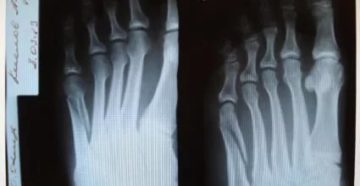

Перелом плюсневой кости стопы – самые эффективные способы диагностики и лечения травмы Перелом плюсневой кости…